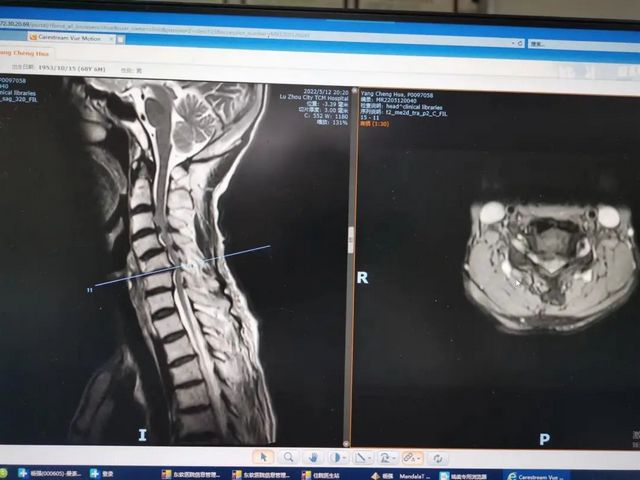

杨先生脊髓性颈椎病拍片

原来,杨先生无明显诱因的出现颈肩部、腰部疼痛,在当地医院住院治疗后症状稍缓解,随后疼痛症状又加重,并反复发作。近日,杨先生状况已是下地行走困难,还伴四肢疼痛、麻木、无力等,为求进一步治疗,杨先生来到泸州市中医医院就诊。经检查,杨先生是患了脊髓性颈椎病加腰椎管狭窄症。